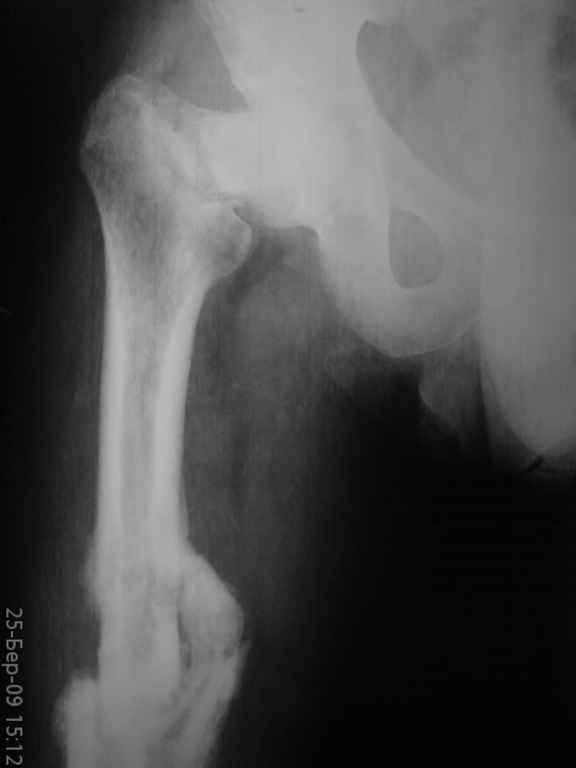

К нам поступил больной,26 лет,травма 6 месяцев назад(падение с

высоты). Лечился консервативно (вытяжение,гипс) по поводу перелома

бедра, перелом шейки был пропущен.

Объективно:ходит с помощью костылей, нога не опорная.Укорочение

приблизительно 6 см, жалуется на умеренные боли при нагрузке в паху и

с/3 бедра.

Ренгенснимки прилагаются(за качество не обессудьте); на КТ с/3 бедра

- формирующийся тугой ложный сустав (извините,не смог представить),

КТ шейки не делали.

Вложение не в текстовом формате было извлечено…

Имя     : DSC00451.JPG

Тип     : image/jpeg

Размер  : 10051 байтов

Описание: отсутствует

Url     : http://weborto.net:8080/pipermail/ortho/attachments/20090329/dbbd3c7a/attachment-0007.jpeg